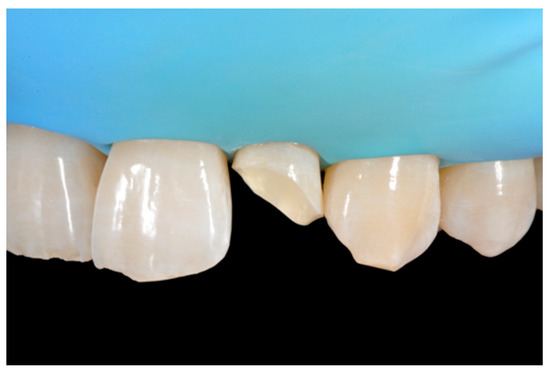

2.6. Case 6

A healthy 23-year-old man referred to the dental office for the esthetic rehabilitation of right central maxillary incisor (Figure 48). Shade was selected as described in previous cases, using the button-try technique [14]. After isolation, preparation (Figure 49) and adhesive procedures (Prime & Bond Active, Dentsply Sirona, York, PA, USA), the frame was completed (Figure 50, Figure 51 and Figure 52) using a silicone index prepared upon a wax-up using translucent and opaque materials (Ceram.x Spectra Effects D1, E1, A1, Dentsply Sirona, York, PA, USA).

Excesses were removed from the frame (Figure 53) and silane and adhesive were applied following the step-by-step procedure described in Section 2.1.2. Dentinal body (Ceram.x Spectra Effects D1, Dentsply Sirona, York, PA, USA) (Figure 54) was applied to reproduce internal anatomy and then the external translucent enamel and body (Ceram.x Spectra Effects E1, A1, Dentsply Sirona, York, PA, USA) were applied checking precisely thickness and removing excesses with a caliper (Figure 55 and Figure 56) (TNCALIBRA, HuFriedy, Chicago, IL, USA). The restoration shows good integration one-year post-operative (Figure 57).